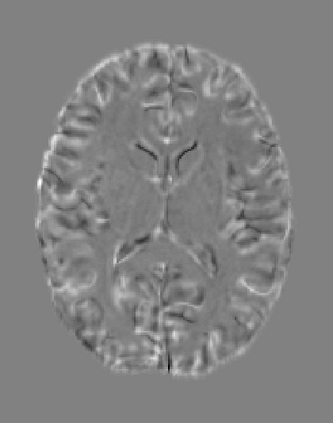

The purpose of this work is to contribute to the state of the art of deep-learning methods for diffeomorphic registration. We propose an adversarial learning LDDMM method for pairs of 3D mono-modal images based on Generative Adversarial Networks. The method is inspired by the recent literature for deformable image registration with adversarial learning. We combine the best performing generative, discriminative, and adversarial ingredients from the state of the art within the LDDMM paradigm. We have successfully implemented two models with the stationary and the EPDiff-constrained non-stationary parameterizations of diffeomorphisms. Our unsupervised and data-hungry approach has shown a competitive performance with respect to a benchmark supervised and rich-data approach. In addition, our method has shown similar results to model-based methods with a computational time under one second.